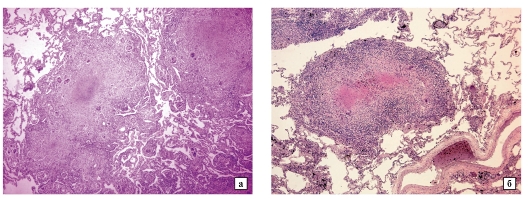

Микроскопический взгляд на мишитарный туберкулез легкого: фотодокументация

Раздел: Снимки-откровения